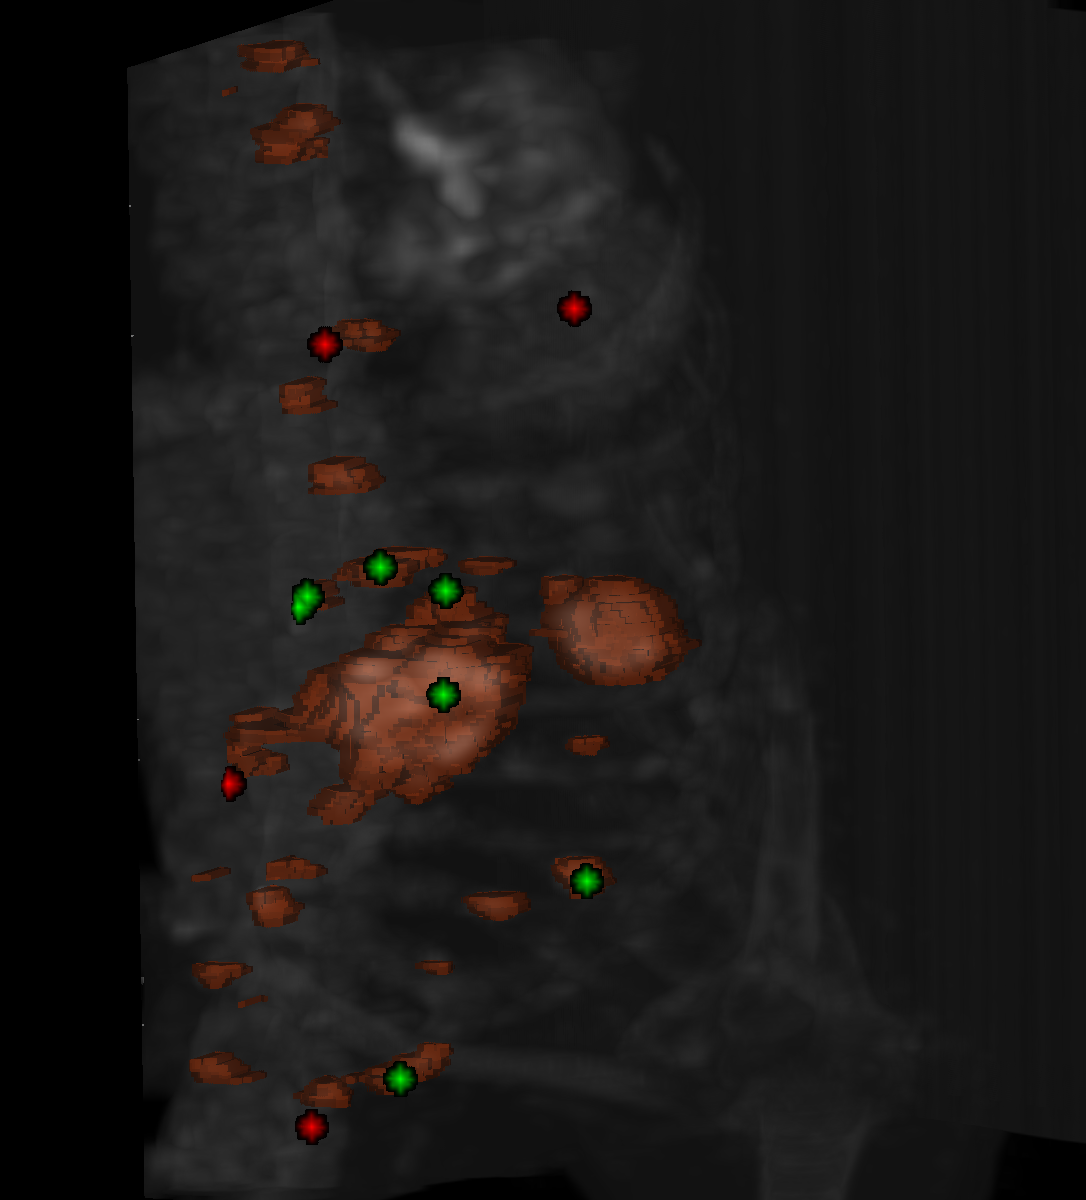

Figure 1: Examplary visualization of 3D image patches provided to the network during training with the respective positive (green) and negative (red) points as well as the ground truth segmentation mask shown.